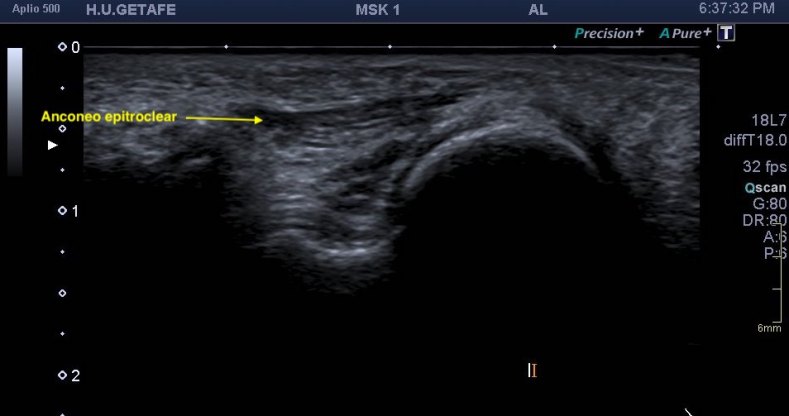

De presentación rara, su aspecto es típico de un músculo, justo encima del canal del cubital, donde normalmente no tiene que haber nada…Mira la normalidad de la anatomía ecográfica del canal cubital:

Para localizar esta ecoarquitectura tienes que trazar una línea imaginaria entre el olécranon y la epitróclea, visible por la orografía del codo y palpables, así que no tiene pérdida. Vas a ver el nervio cubital en un corte axial. Redondo, en forma de panel de abeja, observa la parte superior de la imagen ecográfica donde no existe nada por encima del nervio, justo en esa línea imaginaria que te he pedido que uses para conseguir esta imagen…

Esta semana tenía que ser…una paciente con una sospecha de neuritis del cubital. Efectivamente en el corte idéntico al de la imagen superior, puedes ver un nervio muy aumentado de tamaño, desplazado, pero justo encima de él, superior y en forma de sombrero una imagen hipoecogénica alargada, con aspecto de músculo que no debiera estar ocupando ese espacio.